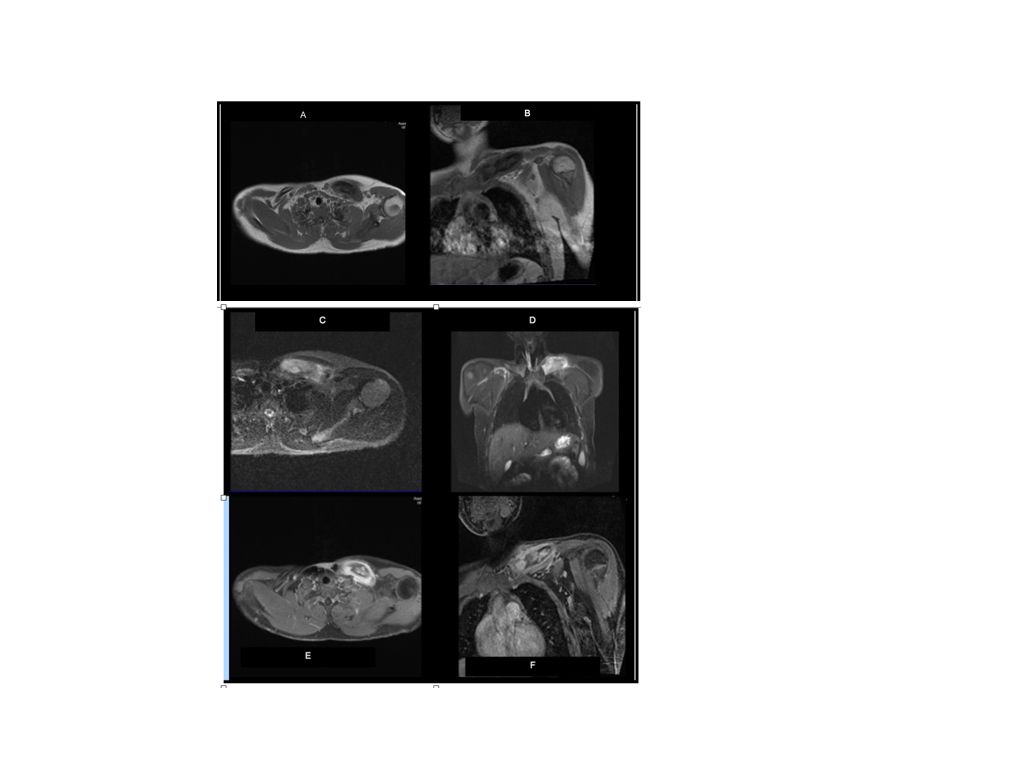

- Epígrafe de RMN

- RMN